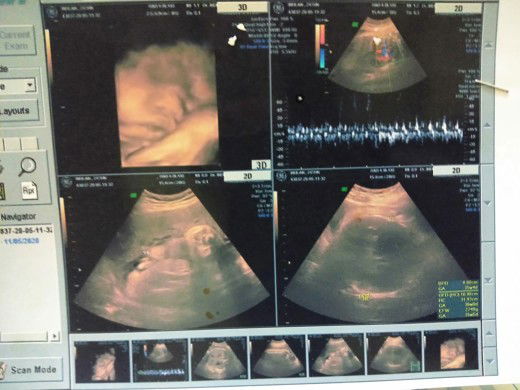

Hamil anak kedua

alhamdulillah

35week5day 2.8 kg bun,uda masuk panggul inshallah gak mutar lagi. Krn tiap pagi rajin gerak drmh,latihan squad 8 kali. Saya lg program VBAC bun,jarak anak prtma 2.5 thn. Skrg lg berusaha supaya cpt kontraksi,yg penting berat uda cukup. VBAC mmng ga disarankan bayi trlalu besar. Pengennya sblm lebaran uda lahiran. Minta doanya bunda2. Semoga yg lg brusaha masuk panggul,jgn lupa rajin squad dan gerak. Lawan malas td ya bun